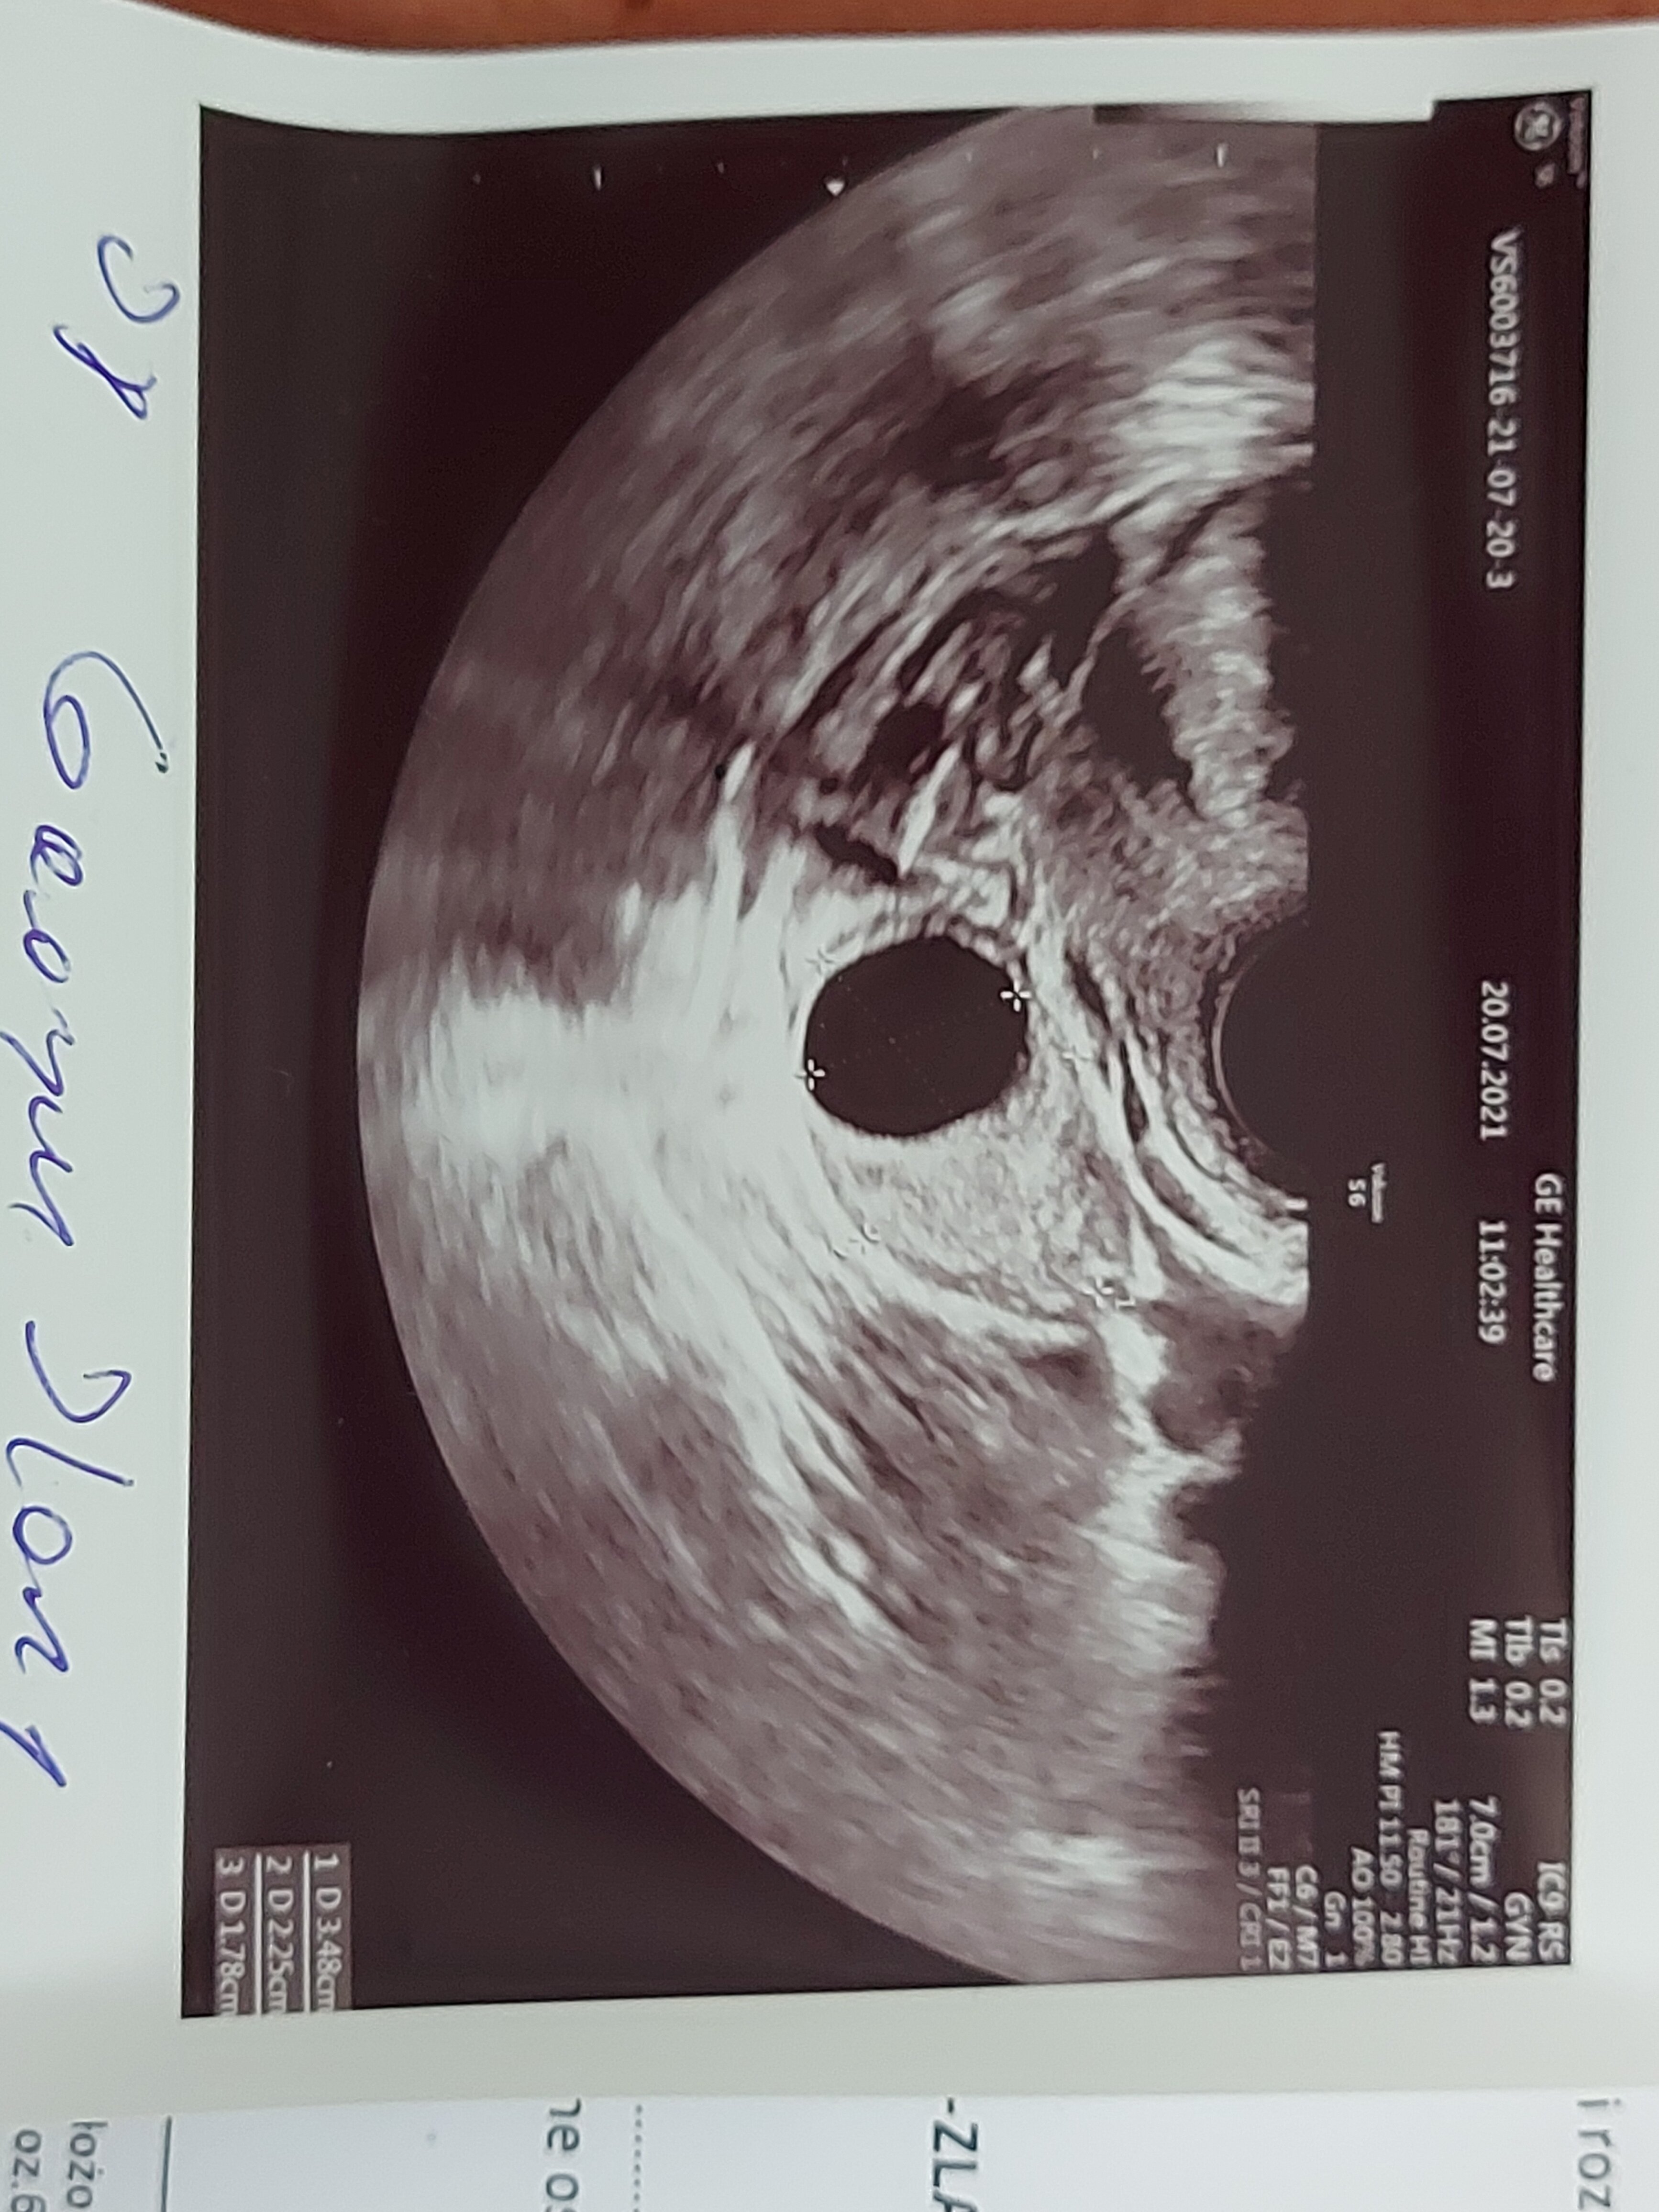

Czesc.Jestem tu od kilku dni i napisalam podobny temat do TwojegoTez jestem 6tyg.Pan doktor który badał mnie prywatnie zlokalizował tylko pęcherzyk.Potem mialam badanie u swojej pani doktor po tygodniu,ale przyjęła mnie inna lekarka w zastępstwie tylko ze z nią miałam spiecie ale to inny temat zbadała mnie szybko i niedokładnie i powiedziała ze obraz niewyraźny płodu itp i dala skierowanie do szpitala mysle że specjalnie to zrobiła by mnie zdenerwować i by mnie od haczyk.Miałyśmy ostra wymianę zdań powiedziala ze mnie nie przyjmie na wizytę bo mam krotkie slodenkiPierwszy raz się spotkalam z czym takim.Dziewczyny na forum pisały mi ze przykro im jak mnie potraktowala i że nie mam się przejmować i poradziły że mam poczekac bo u nich zarodek pokazał się w 7 i 8 tyg i że mam byc cierpliwa.Jutro idę z polecenia kolezanki to superr specjalisty i dowiem się więcej.Takze mysle ze po prostu czas pokaze nam...Bądźmy dobrej mysli.Ściskam ciepło.